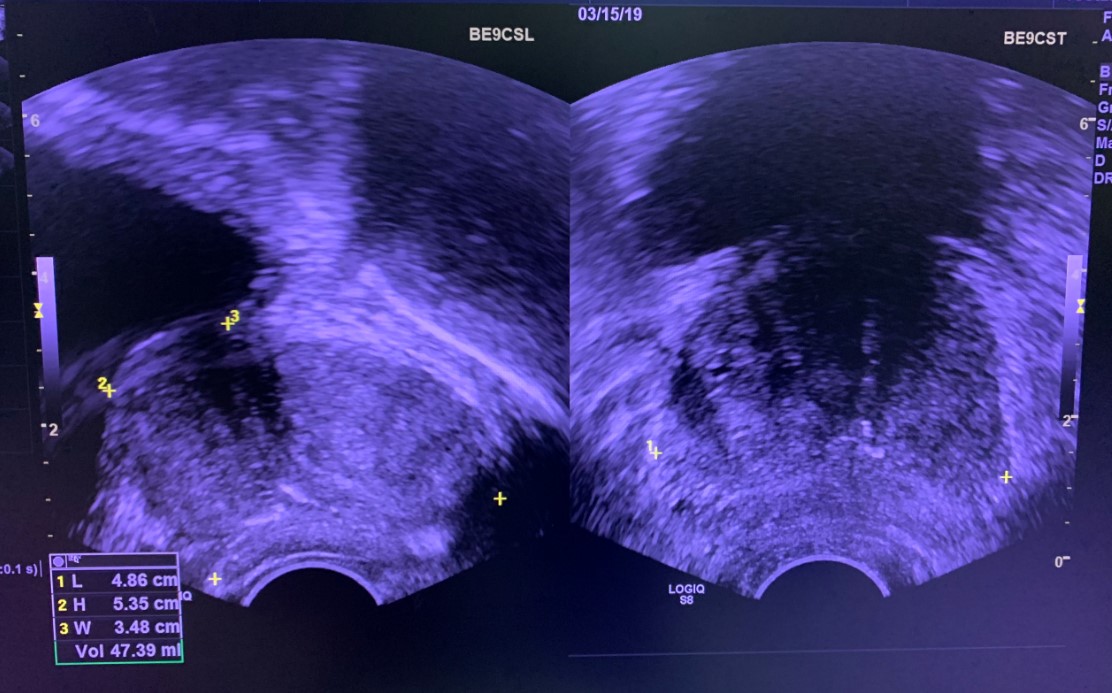

Hình ảnh ca sinh thiết tuyến tiền liệt dưới hướng dẫn đầu dò trực tràng

Đây là kỹ thuật lấy mảnh bệnh phẩm từ mô tuyến tiền liệt được thực hiện dưới hướng dẫn của đầu dò siêu âm qua đường trực tràng (hình ảnh siêu âm trực tiếp bởi đầu dò siêu âm đi vào trong trực tràng).